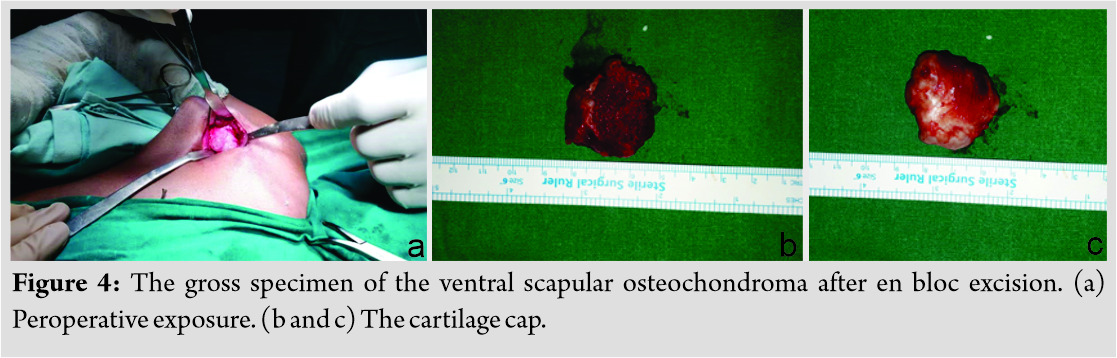

On examination, there was a single swelling of approximately 3 × 3 × 2 cm3 over medial border of the left scapula. Overlying skin was normal. It was hard in consistency with well-defined margin and irregular surface. It was non-tender, immobile, arising from underlying bone, and non-adherent to skin. It was non-fluctuant and non-compressible. Pseudo-winging of scapula was present as shown in (Fig. 1) with wall test because there was no tenderness, neurological examination was within normal limit, and range of movement in cervical spine along with extremity was normal. His activity of daily living was not affected. There were no signs of compression of nerves, vessels, or lymphatic system. No lymph nodes were palpable. Distal neurovascular status was within normal limit. There was no audible or palpable crepitus. Range of movement of the shoulder and cervical spine was normal. The patient was referred with an anteroposterior view radiograph and a computed tomography (CT) scan. No further radiological workup was attempted in view of radiation exposure. The CT scan demonstrated a well-corticated bony excrescence arising from ventral surface of the left lower part of body of scapula near inferior angle suggestive of exostosis (Fig. 2). A working diagnosis of VSO was made. Excision of lesion was principally done for mechanical reasons and secondarily for pathologic assessment. It was done under general anesthesia with patient in prone position. Shoulder was rotated internally, which helped lift medial border of scapula. A 5 cm incision was given along inferomedial border. A muscle splitting approach of trapezius and rhomboid was used. En bloc excision of VSO was done. To prevent complications, meticulous dissection was done and hemostasis was obtained. It was removed as a single block to prevent seeding. No remnants were left. Sessile VSO of 3 × 3 × 1 cm3 was sent for histopathological assessment. The tumor was hard. It was composed of bone covered by a thick cartilage cap, as shown in (Fig. 3, 4). Thorough irrigation was done and the wound was closed in standard fashion. The surgery was over in 45 min.

A working diagnosis of VSO was made. Excision of lesion was principally done for mechanical reasons and secondarily for pathologic assessment. It was done under general anesthesia with patient in prone position. Shoulder was rotated internally, which helped lift medial border of scapula. A 5 cm incision was given along inferomedial border. A muscle splitting approach of trapezius and rhomboid was used. En bloc excision of VSO was done. To prevent complications, meticulous dissection was done and hemostasis was obtained. It was removed as a single block to prevent seeding. No remnants were left. Sessile VSO of 3 × 3 × 1 cm3 was sent for histopathological assessment. The tumor was hard. It was composed of bone covered by a thick cartilage cap, as shown in (Fig. 3, 4). Thorough irrigation was done and the wound was closed in standard fashion. The surgery was over in 45 min.

Treatment